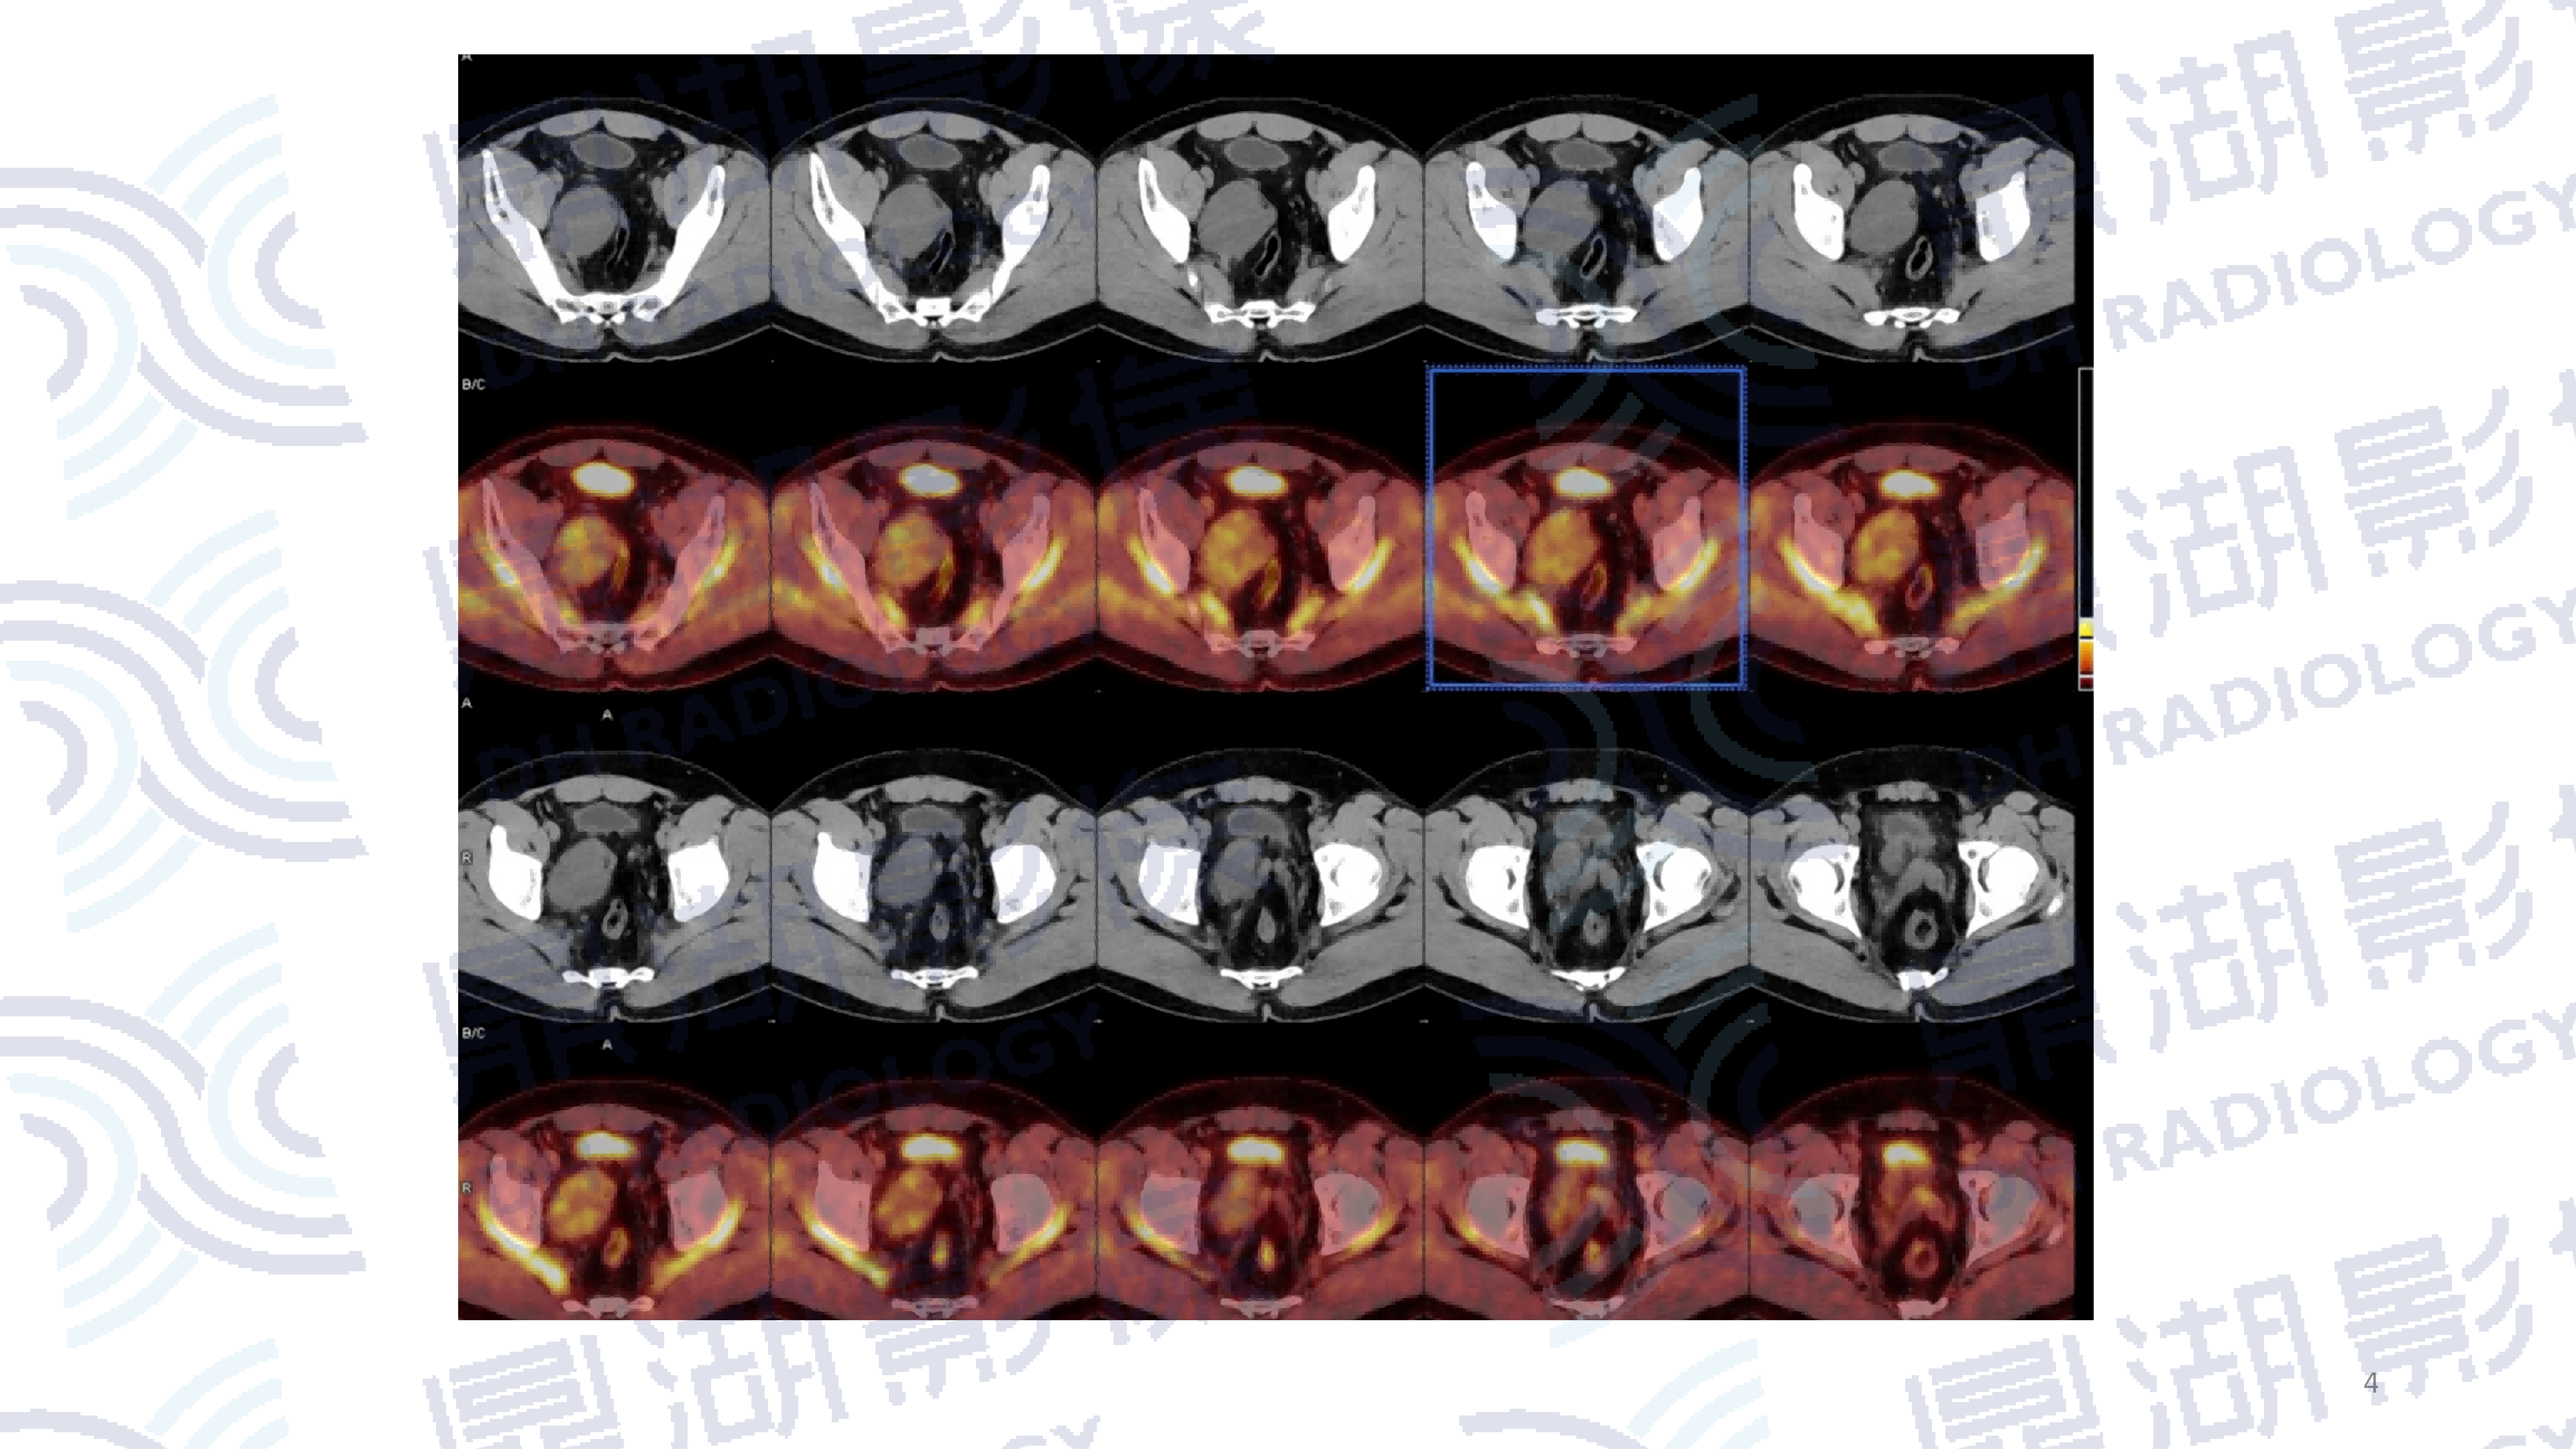

患者,女性,80岁

主诉:左侧肢体无力2周

现病史:患者两周前发现无明显诱因左侧肢体无力、行走不稳伴发热,表现为走路向左侧偏斜,无恶心呕吐,一直未予以治疗。

既往史:无高血压、糖尿病病史;无传染病病史

查体:无明显异常